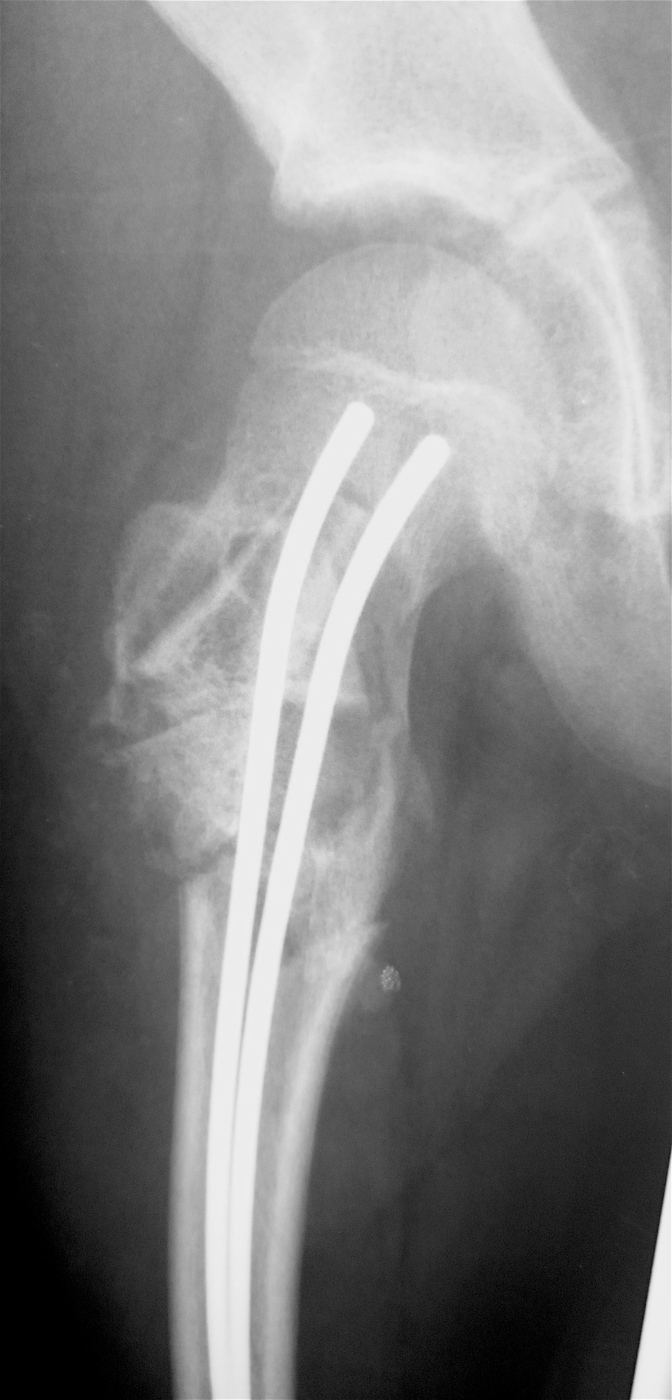

Выполнена резекция с аллопластикой губчатыми и кортикальными биоимплантатами "Лиопласт".